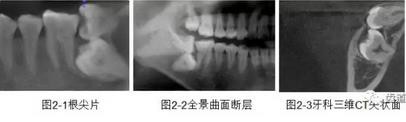

2、下頜磨牙阻生

下頜第二第三磨牙阻生口腔曲面斷層片影像

下頜第二第三磨牙阻生CBCT影像定位

三種圖片的影像學(xué)比較